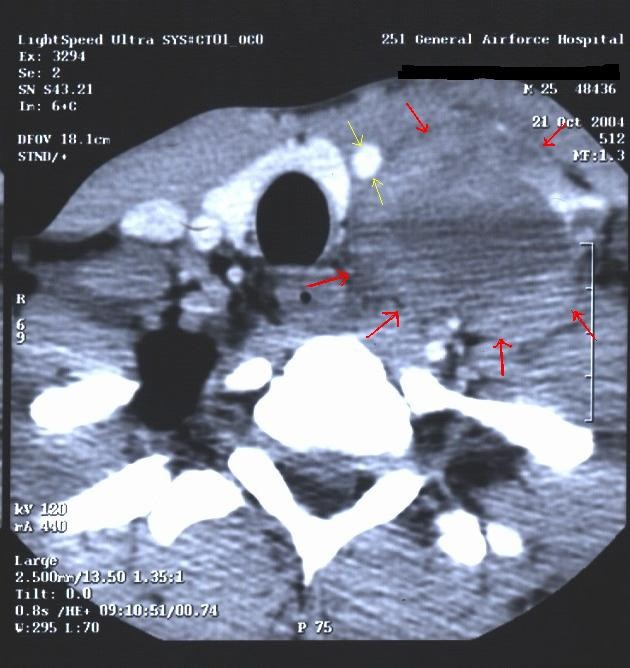

A 25-year-old male was presented in October 2004 with a monthly history of a gradually enlarging, painless, left cervical mass. He had no history of prior thyroid disorder or other disease. Clinically the mass was hard in palpation, firmly attached to the surrounding tissues and was located at the anatomic area of the carotide triangle. Thorough physical examination revealed only a marginal hepatomegaly and splenomegaly. Routine blood tests, biochemical markers and thyroid function tests – including triiodothyronine (T3), thyroid stimulating hormone (TSH), thyreoglobulin and anti-thyroid antibodies- were within normal limits, with the exception of a moderately elevated erythrocyte sedimentation rate (ESR = 44). Subsequent cervical and thoracic CT scan revealed a multilobular mass (4,3 × 4,7 × 7 cm) probably arising from the left thyroid lobe, with infiltrating features and heterogeneous density with regions of central necrosis and hemorrhage. The mass submerged into the anterior-posterior mediastinum, in proximity with the great vessels of the heart, dislocating the left common carotid artery and the left vagus nerve without infiltrating them (Fig. 1 and 2). Significant mediastinal lymphadenopathy was also noted, whereas ultrasound of the abdomen excluded liver involvement. Differential diagnosis included thyroid carcinoma, lymphoma, thymoma, malignant congenital branchiac cyst or cystic hygroma and germ cell tumours of the upper mediastinum. Fine-needle aspiration biopsy of the cervical mass was performed and the cytological findings were consistent with papillary thyroid carcinoma with anaplastic features. Based on these findings, the patient was referred for surgical removal of the lesion. At surgery, a large mass, measuring 9,5 × 6,3 × 4,5 cm was found behind the left srenocleidomastoid muscle, located lateral to the left carotid artery/jugular vein and was not firmly adhered to the left thyroid lobe. The mass was easily separated from the surrounded tissues and was removed. Based on the results of preoperative fine needle aspiration biopsy, a total thyroidectomy was performed at the same time. Pathology examination of the mass revealed extensive infiltration by large or giant malignant cells with morphological features consistent with syncytiotrophoblasts within necrotic and hemorrhagic elements (Fig. 3A). Positive immunohistochemical staining with β-subunit of human chorionic gonadotrophin (β-hCG) suggested the diagnosis of choriocarcinoma of the upper mediastinum (Fig. 3B). The pre-operation serum concentration of β-hCG was >100.000 mIU/ml, whereas the immediate post-operation levels declined to 17.300 mIU/ml. Alpha- fetoprotein (a-FP) and carcinoembryonic antigen (CEA) levels were within normal limits, while lactate dehydrogenase (LDH) level was two-fold higher than the normal upper limit. Based on these data, scrotal ultrasound examination was performed, disclosing a small multilobular mass measuring 2,1 cm in greatest diameter-not evident at previously performed physical examination- located on the upper pole of the left testicle with echomorphological and hemodynamic characteristics consistent with seminomatous tumour. Subsequently, the patient underwent left radical inguinal orchiectomy with high ligation of the left spermatic cord and implantation of synthetic testicular prothesis. Histological diagnosis of the testicular tumour revealed almost typical seminoma (1,8 × 1,2 × 1 cm) consisting of large clear-cytoplasm cells with hypodense nucleus and a few atypical mitosis, without any signs of infiltration of rete testis or the spermatic cord. Complete inhibition of spermatogenesis and hyperplastic reaction of Leydig cells were also observed (Fig. 4A). Although immunohistochemical staining for β-hCG was positive in a few cells, their morphological characteristics did not meet the diagnostic criteria for syncytiotrophoblasts (Fig. 4B). On postoperative day six (6), the patient developed slightly painful cervical mass at the anatomic site of the first surgical intervention and β-hCG levels started rising up again (β-hCG = 29.850 mIU/ml) (Fig. 5). Complete pre-therapeutic staging was immediately performed, including negative CT scan of the brain and negative bone scan, whereas CT scan of the thorax and the abdomen disclosed multiple round metastatic nodules of various size (0,1 – 2 cm) in both lungs and marginally enlarged iliac and para-aortic lymph nodes without liver or other parenchymal organ involvement. In November 2004, one month after his initial admission to the hospital, the patient received 1st line chemotherapy for high-risk germ cell tumour with the BEP regimen (Bleomycin 30 mg: d1-d8-d15, Etoposide 100 mg/m2: d1-d5 and Cisplatin 20 mg/m2: d1-d5 in 21-day cycles). Pre-chemotherapy levels of β-hCG were 93.400 mIU/ml. The patient completed 4 cycles of therapy without experiencing remarkable toxicity (Neutropenia grade I-II according to the NCI-CTC criteria) and is currently (October 2006) asymptomatic, with ongoing complete clinical and biochemical remission according to the RECIST criteria (No evidence of tumour mass, regression of all enlarged lymph nodes, necrotic post-chemotherapy elements in the remaining lung nodules confirmed by CT-guided fine-needle aspiration biopsy and PET scan and consecutively normal levels of β-hCG). A schematic presentation of the whole diagnosis and treatment course including β-hCG titer and chest Xray findings is illustrated in Fig. 5

CT scan of the cervix revealing a large mass (red arrows), 14 cm in greatest diameter extending from the left carotide triangle to the anterior-posterior mediastinum, in proximity with the great vessels of the heart, dislocating the left common carotid artery (yellow arrows) and the left vagus nerve without infiltrating them.